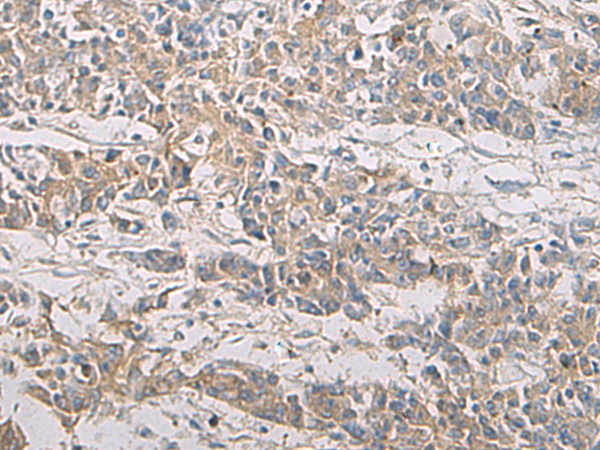

分类: 科研抗体货号: P03372别名: RDH1; 9cRDH; SDR9C5; HSD17B9应用: IHC反应种属: Human, Mouse